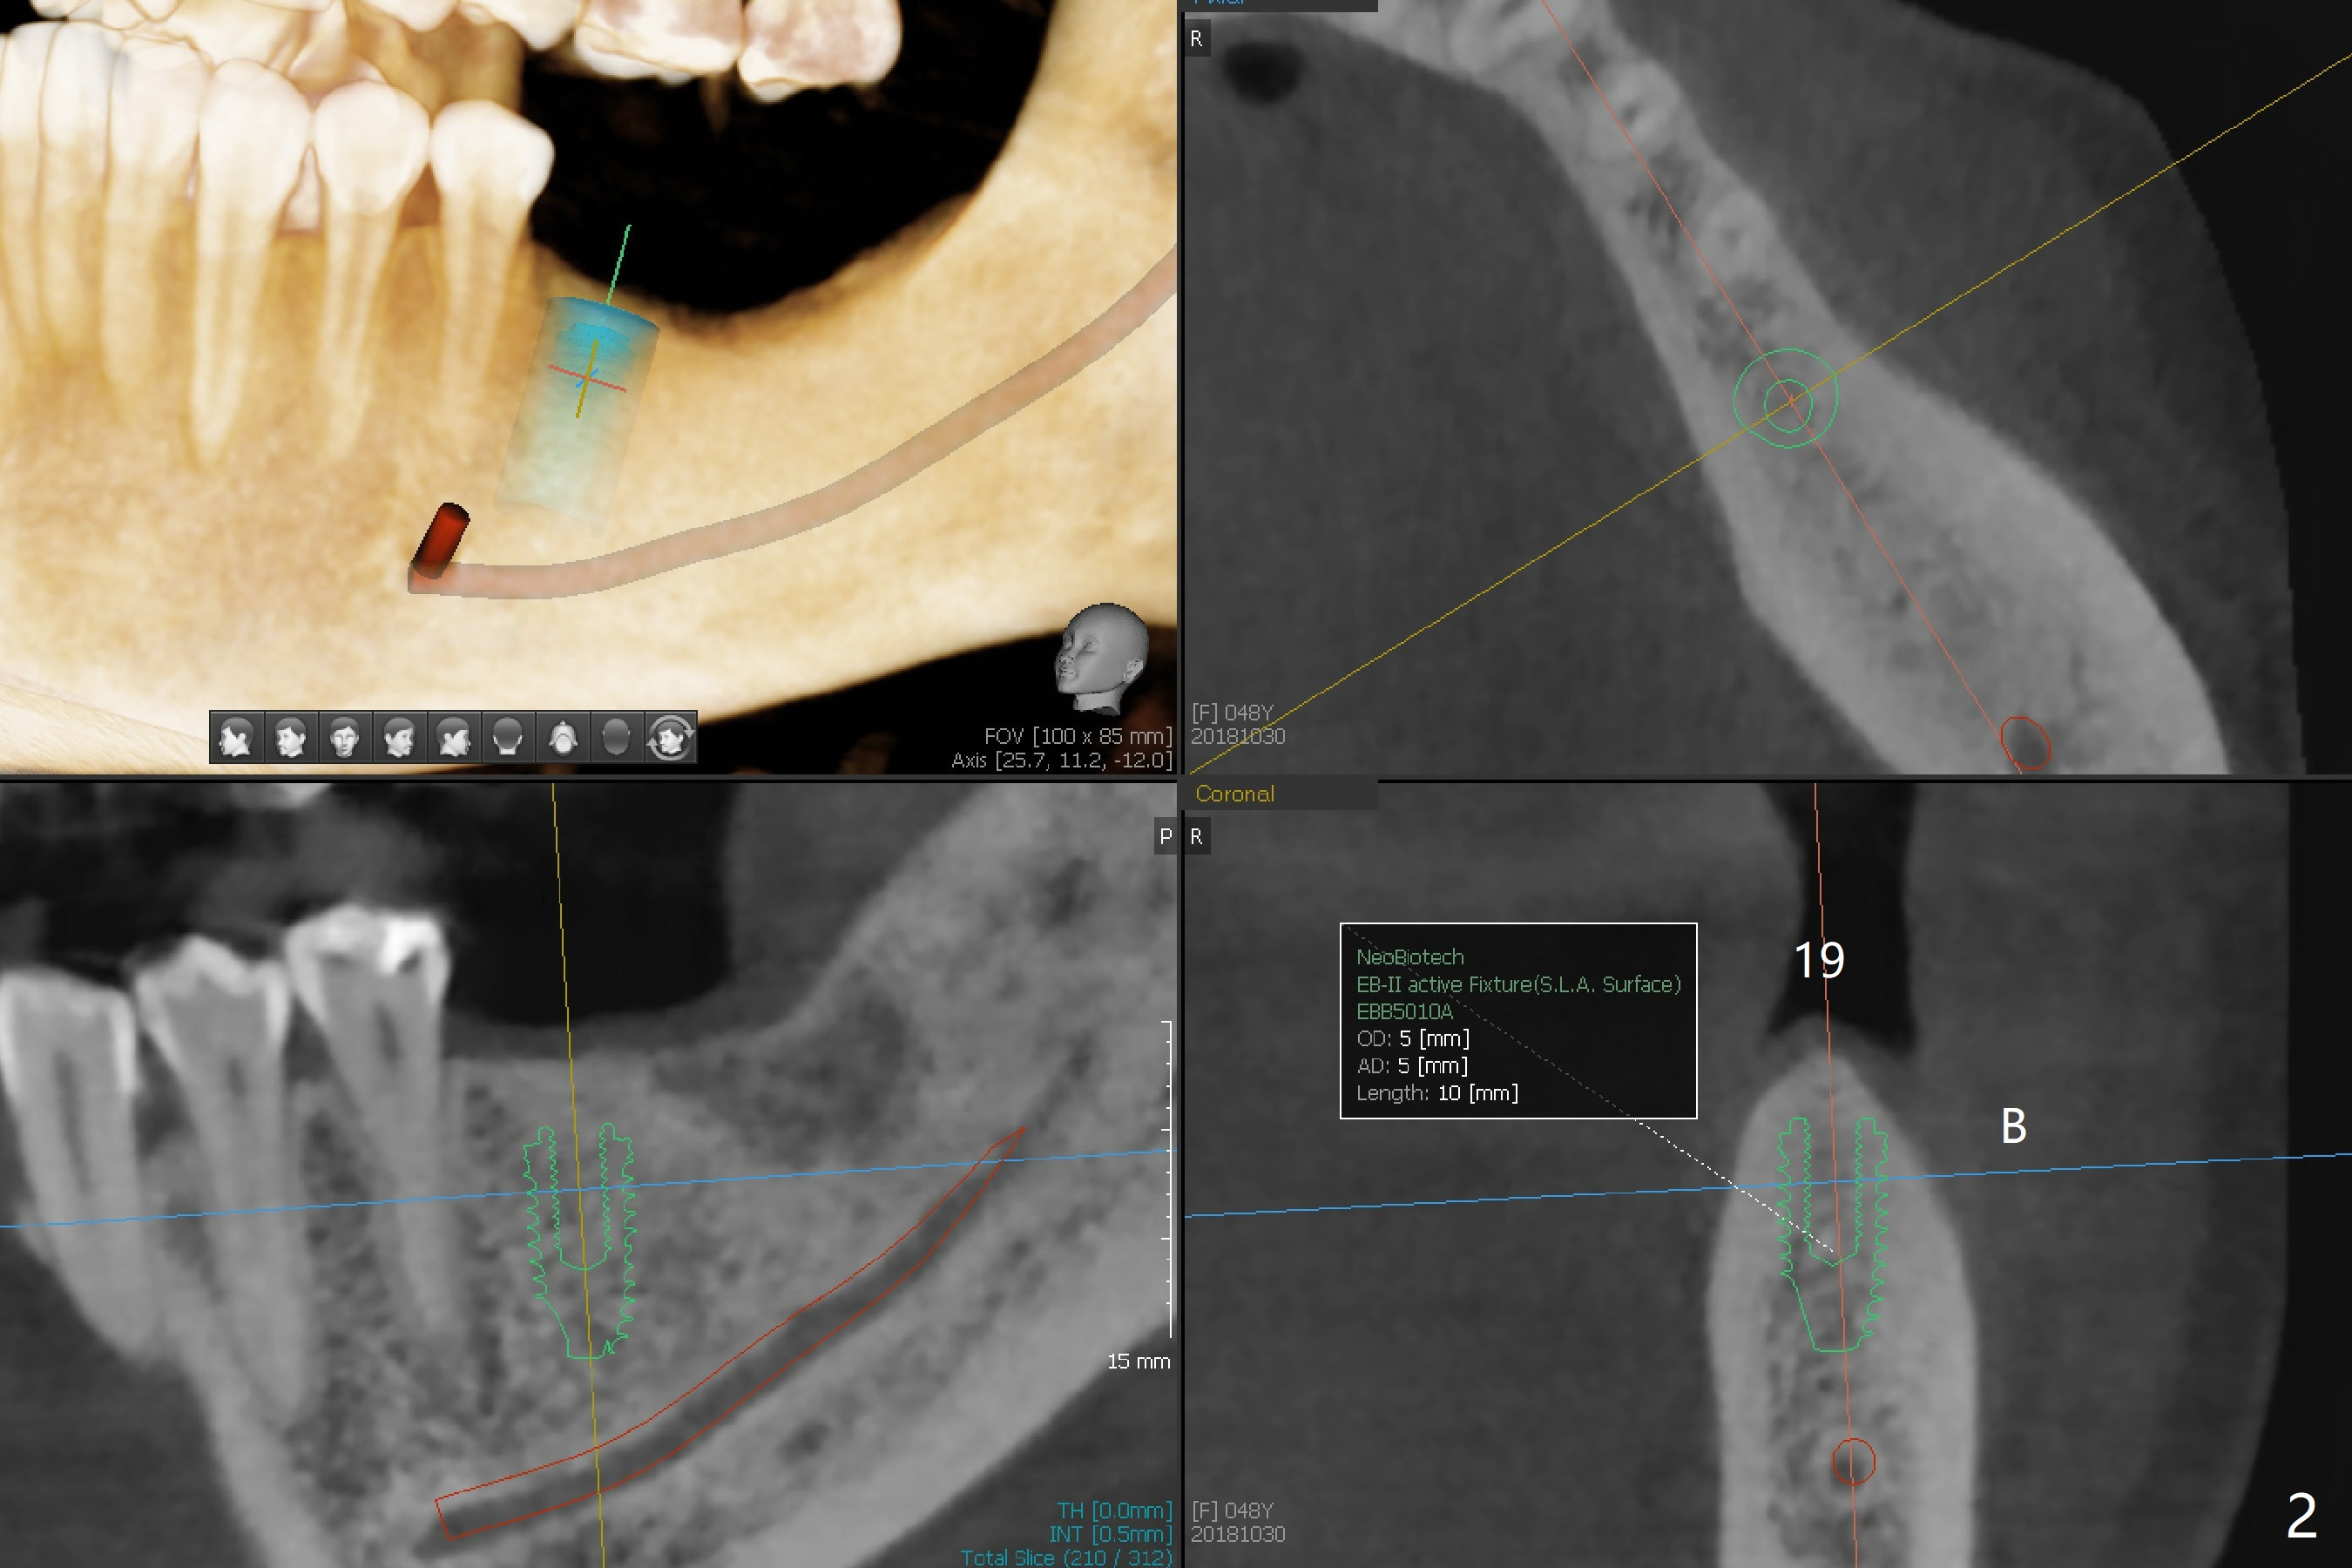

A 48-year-old woman, dentophobic, presents to clinic with request of redo #8,9 composite, which have dislodged twice in the last 6 months. Restoration failure is at least in part due to partial edentulism (#18,19,30, Fig.1). After discussion, she agrees to have implants at #18 and 19 first with guide (Fig.2,3). An ideal treatment plan for #30 (narrow mesiodistal space) would be extraction of #32 (ML fracture), uprighting of #30 and placement of a normal diameter implant. Considering dentophobia and living far from the office, a practical option will be a 3x12 mm 1-piece implant (Fig.4).